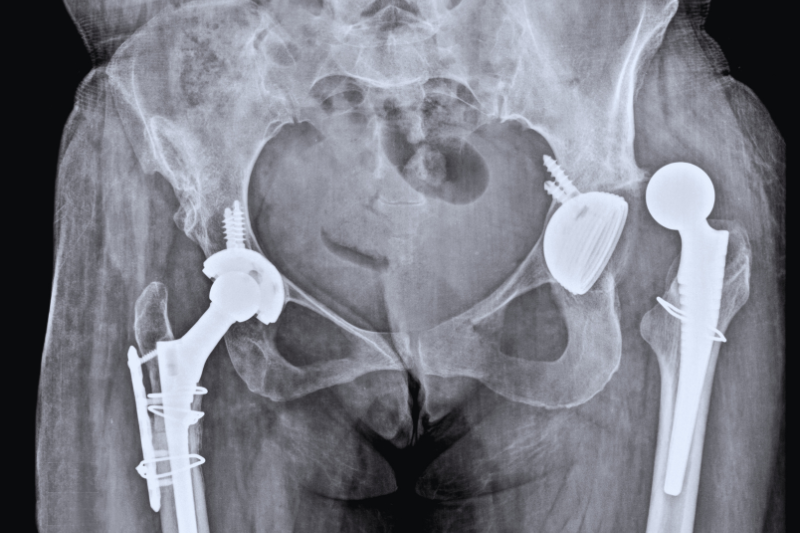

Understanding Hip Replacement Surgery

Hip replacement involves removing the damaged ball-and-socket components of the hip joint and replacing them with biocompatible artificial implants. The procedure can be either total hip replacement (both ball and socket replaced) or partial hip replacement (only the ball). Using minimally invasive techniques, our surgeons ensure reduced blood loss, minimal tissue disruption, and faster recovery.